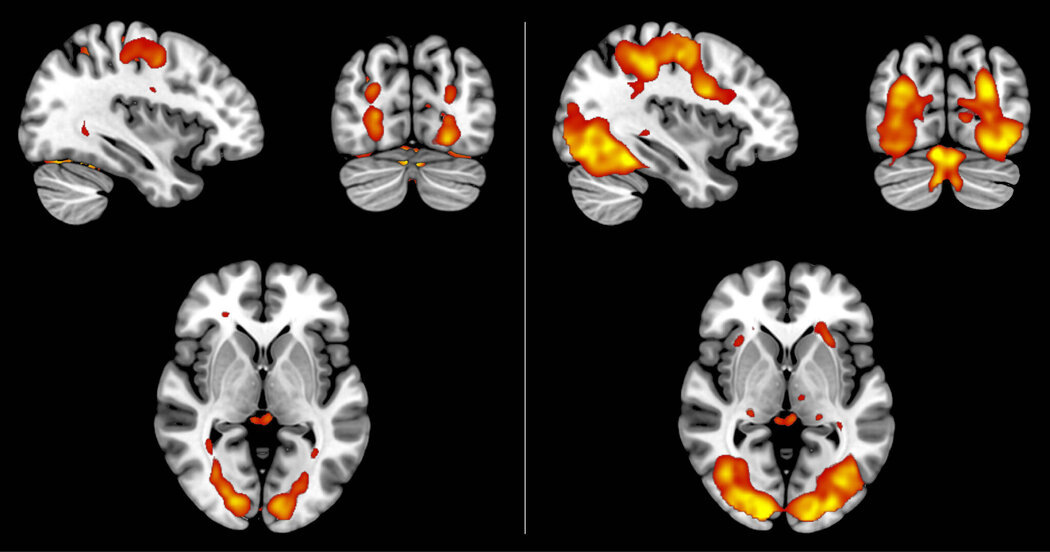

Сканирование функций мозга показывает, что воображаемые и воспринимаемые изображения запускают схожие модели активности, но сигналы для воображаемых изображений слабее (слева).

Источник: Dijkstra, N.Subjective signal strength...